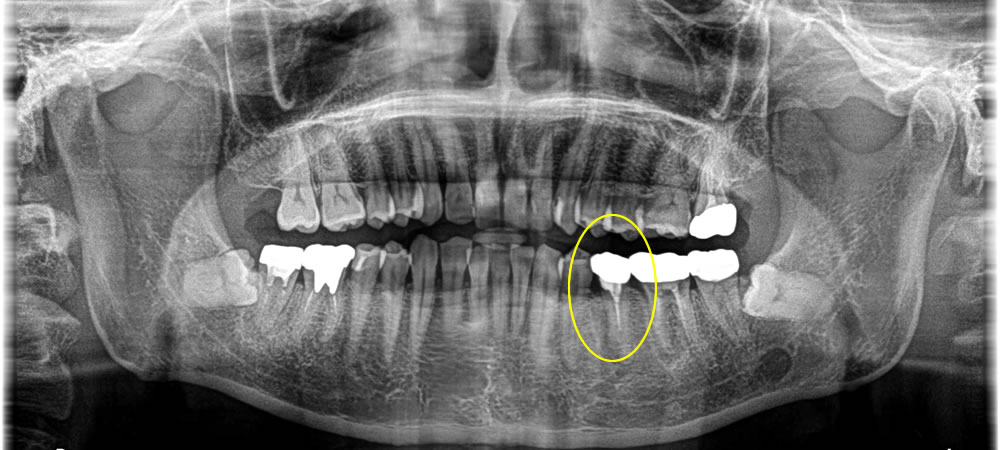

歯根破折した歯を抜歯してインプラント治療を行った症例

年齢

30代

性別

男性